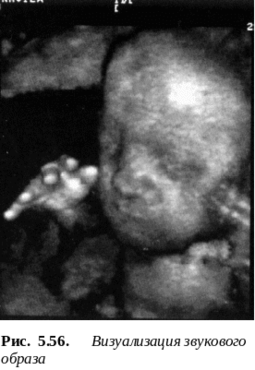

простейшем случае одномерного сканирования объект облучается УЗ в импульсном режиме, а отраженные от неоднородностей сигналы воспринимаются обратимым ЭАП (рис. 5.55). Амплитуда сигнала зависит от многих факторов: длины волны , затухания , размеров дефекта и расстояния до него х. При качественных оценках амплитуда отраженного импульса u пропорциональна величине дефекта, а временной отрезок до него Тв - глубине его залегания х. Высокоинтенсивные УЗ устройства широко используются в медицине, что даже привело к появлению целой ее отрасли - УЗ хирургии. Фокусированное излучение, создаваемое УЗ концентраторами (рис. 5.50) целесообразно для создания локальных разрушений в глубинных тканях организма, например, в структурах головного мозга [ ]. Другой областью медицины являются УЗ исследования (УЗИ). Средствами УЗИ диагностируются патологии во внутриутробном развитии, в строении внутренних органов и т.д. (рис. 5.56) Чрезвычайно эффективна УЗ компьютерная томография, позволяющая получать двух- и трехмерные изображения различных областей организма. Схема прибора приведена на рис. 5.57. В томографе применяется обратимая УЗ матрица (многоэлементная решетка), содержащая до 10000 точечных преобразователей. Рабочая поверхность матрицы смазывается гелем и прикладывается непосредственно к телу пациента. Каждый из преобразователей формирует узкий пучок УЗ излучения в диапазоне частот 2 … 10 МГц, который, проходя сквозь мягкие ткани, отражается от более плотных. Устройства приемо-передачи и управления режимами обеспечивает временную селекцию сигналов и фокусировку излучения на конкретном органе. Для этого в конструкцию излучателя входит 2-х или более линзовый акустический объектив, формирующий звуковой рельеф контролируемого объекта (распределение звукового давления) в плоскости электроакустического преобразователя (рис. 5.56). Большую часть времени томограф работает на прием: время посылки составляет 5 … 10% времени приема.